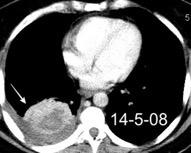

Nefrectomia derecha en 1996 por adenocarcinoma renal. Reseccion de metastasis pulmonar en LSI de carcinoma renal. Sospecha de nueva metástasis.

Granuloma de cuerpo extrano por hilo de sutura en situación cisural